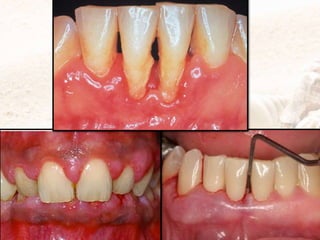

CLINICALFEATURES

1.Various degrees of bluish red

discoloration.

-Flaccidity.

-Smoothshiny surface.

-Pitting on pressure.

2.Gingival wall may be pink and firm.

3.Bleeding on probing.

4.Onprobing inner aspectof wall is

generallypainful.

5.Pus may be expressedon applying

digital pressure.